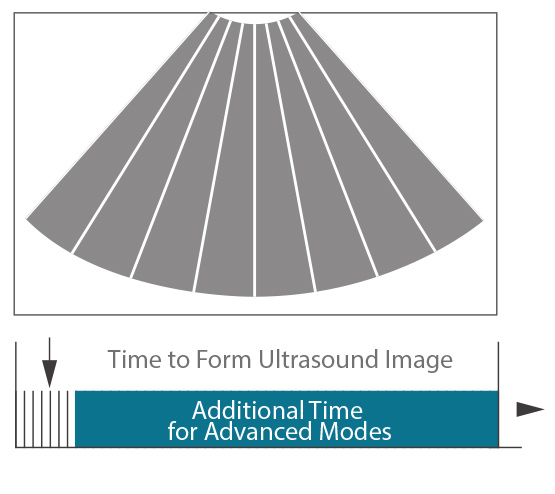

Imágenes de zona

Zone Imaging puede transmitir y recibir un número relativamente menor de zonas ecográficas más grandes, para capturar imágenes en tiempo real de animales de todas las especies.

Adquisición línea por línea

Conformación de vigas tradicional

Adquisición acústica avanzada

Tecnología ZONE Sonography™+